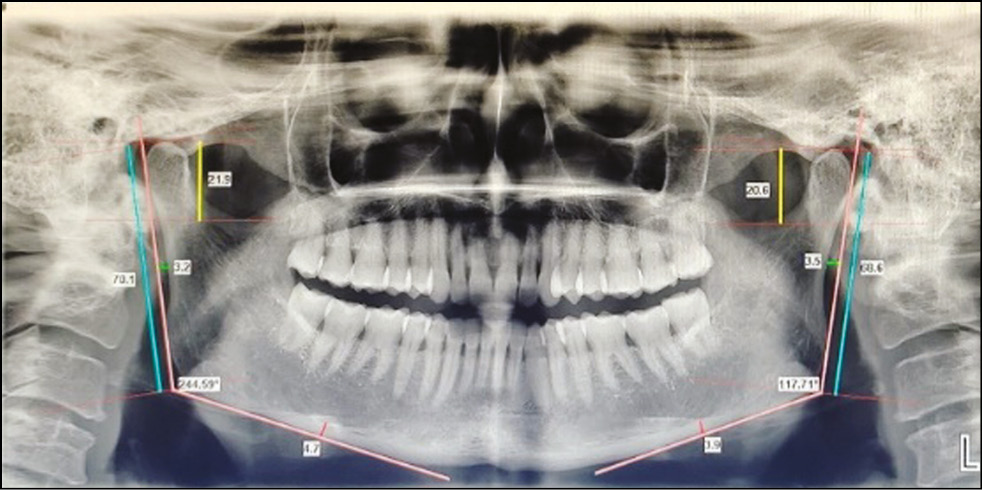

The parameters that were measured in our study were as follows: (Fig. 1)

Fig. 1. All linear and angular parameters on OPG using Planmeca Romexis Software

1) Gonial angle (GA): It is formed by drawing a line between two imaginary lines that extend from the inferior border of the mandible to the ramus of the mandible.

2) Condylar length (CL): It is the distance between two lines drawn tangentially, one at the superior most point of the condylar head and the other at the deepest point of the sigmoid notch’s concavity.

3) Ramus length (RL): It is calculated by drawing two lines, one parallel to the ramus tangent line at the level of the most lateral image of the condyle and the other parallel to the ramus tangent line at the level of the most lateral image of the ramus. The distance between these two lines is RL.

4) Cortical bone thickness: The thickness of the radiopaque band is measured at the lower border of the mandible’s body, where the antegonial notch begins mesially.

5) Ramal notch depth (RND): It is the distance between the ramus tangent line and the ramus notch concavity’s deepest point.